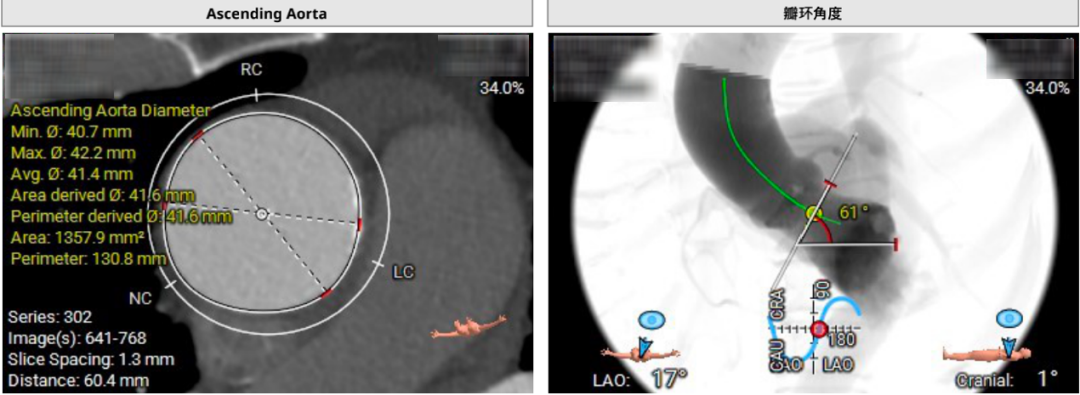

主动脉根部CTA

瓣环周长72.1mm,平均径22.9mm,LVOT周长75.6mm,平均径24.1mm。股动脉入路迂曲,分叉高度可。髂总、腹主动脉团块钙化分布。左侧血管平均最小内径7.2mm,右侧血管平均最小内径6.5mm。左冠高度低,瓣叶长,窦宽相对瓣膜可。右冠高度可,瓣叶长度可,窦宽相对瓣膜可。

手术策略

钱福东教授总结道,该病例特点为三叶式主动脉瓣,重度钙化伴中度反流,综合评估冠脉风险低,瓣叶钙化较重,存在瓣周漏风险。考虑22mm球囊预扩,TAV24瓣膜,备27瓣膜;若球囊无腰征,且存在瓣周漏,建议TAV27瓣膜。倾向右侧股动脉为主入路,选用VitaFlow Liberty™电动可回收瓣膜输送系统。

置于TAV27瓣膜输送系统,主动脉根部造影,定位输送系统位置。